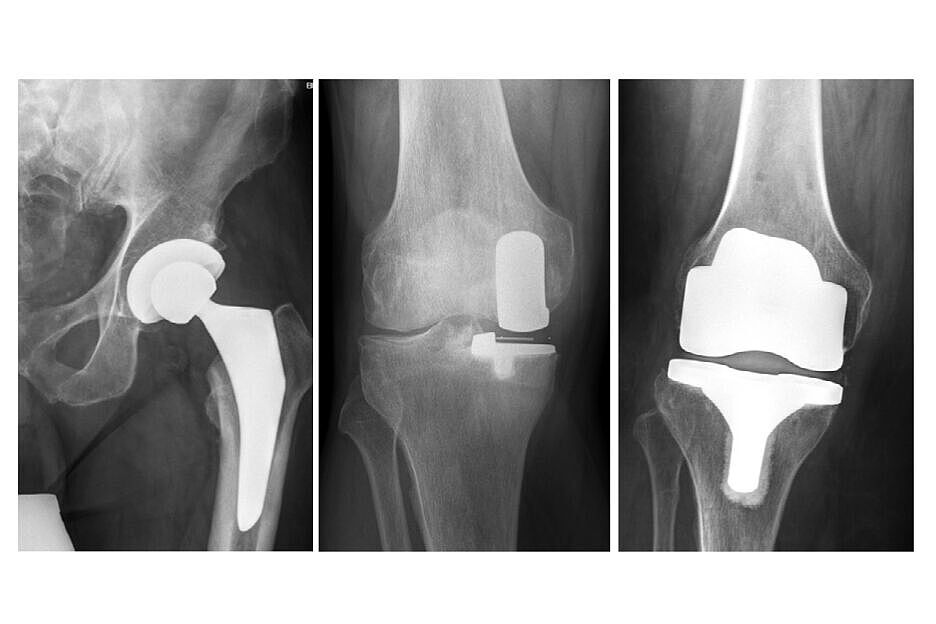

Quelle: BG Klinik Tübingen – Röntgenbilder einer Hüft-Totalendoprothese,

einer Schlittenprothese am Kniegelenk und einer Knietotalendoprothese